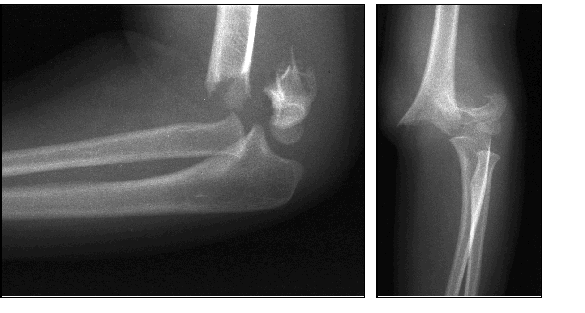

Behandlungen von Schulter-, Ellbogen- und Handgelenks-verletzungen sind oft sehr anspruchsvoll und komplex. Deshalb ist mit einer längeren Erholungsphase in vielen Fällen bis zu 6 Monaten und länger zu rechnen, beispielsweise bei Operationen bei Schulterluxationen und Instabilitäten am Schultergelenk, Schultergelenksarthroskopien bei Einklemmungssyndromen, Rekonstruktion der Rotatorenmanschette, Kunstgelenk-ersatzoperationen an der Schulter. Die Entwicklungen auf diesem Fachgebiet sind enorm vorangeschritten, sodass heute viele Eingriffe in entsprechender arthroskopischer oder minimal-invasiver Technik durchgeführt werden können. Dies führt in der Regel zu bedeutend kürzeren Spitalaufenthalten und schnellerer Erholung.

Die  wichtigsten Verletzungen und Erkrankungen an Schulter, Ellbogen und Hand: